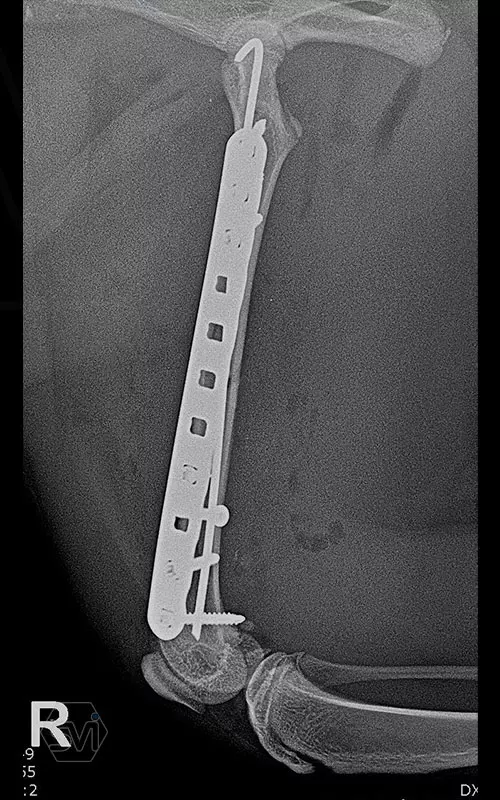

The plates are made in two types: the cutable ones, presented earlier, and the straight plates discussed here. The plates are made of 2 mm thin material and the hole is designed to accept the new 2.0 mm torx head threaded screws and the already used 2.4 mm torx head screws. As our case shows, the two screw sizes can be freely combined within one operation, according to the surgeon's needs. The screws require a T8 torx screwdriver. Of course, the plate can accept traditional AO screws as well.

In our case, a middle third fragment fracture of a 10-month-old kitten was treated with a 2.0 polyaxial plate and a combination of 2.0 and 2.4 screws.

Esetünkben egy 10 hónapos cica középső harmadiszilánkos törését kezeltük 2,0 poliaxiális lemezzel és 2,0 és 2,4 csavarok kombinációjával.